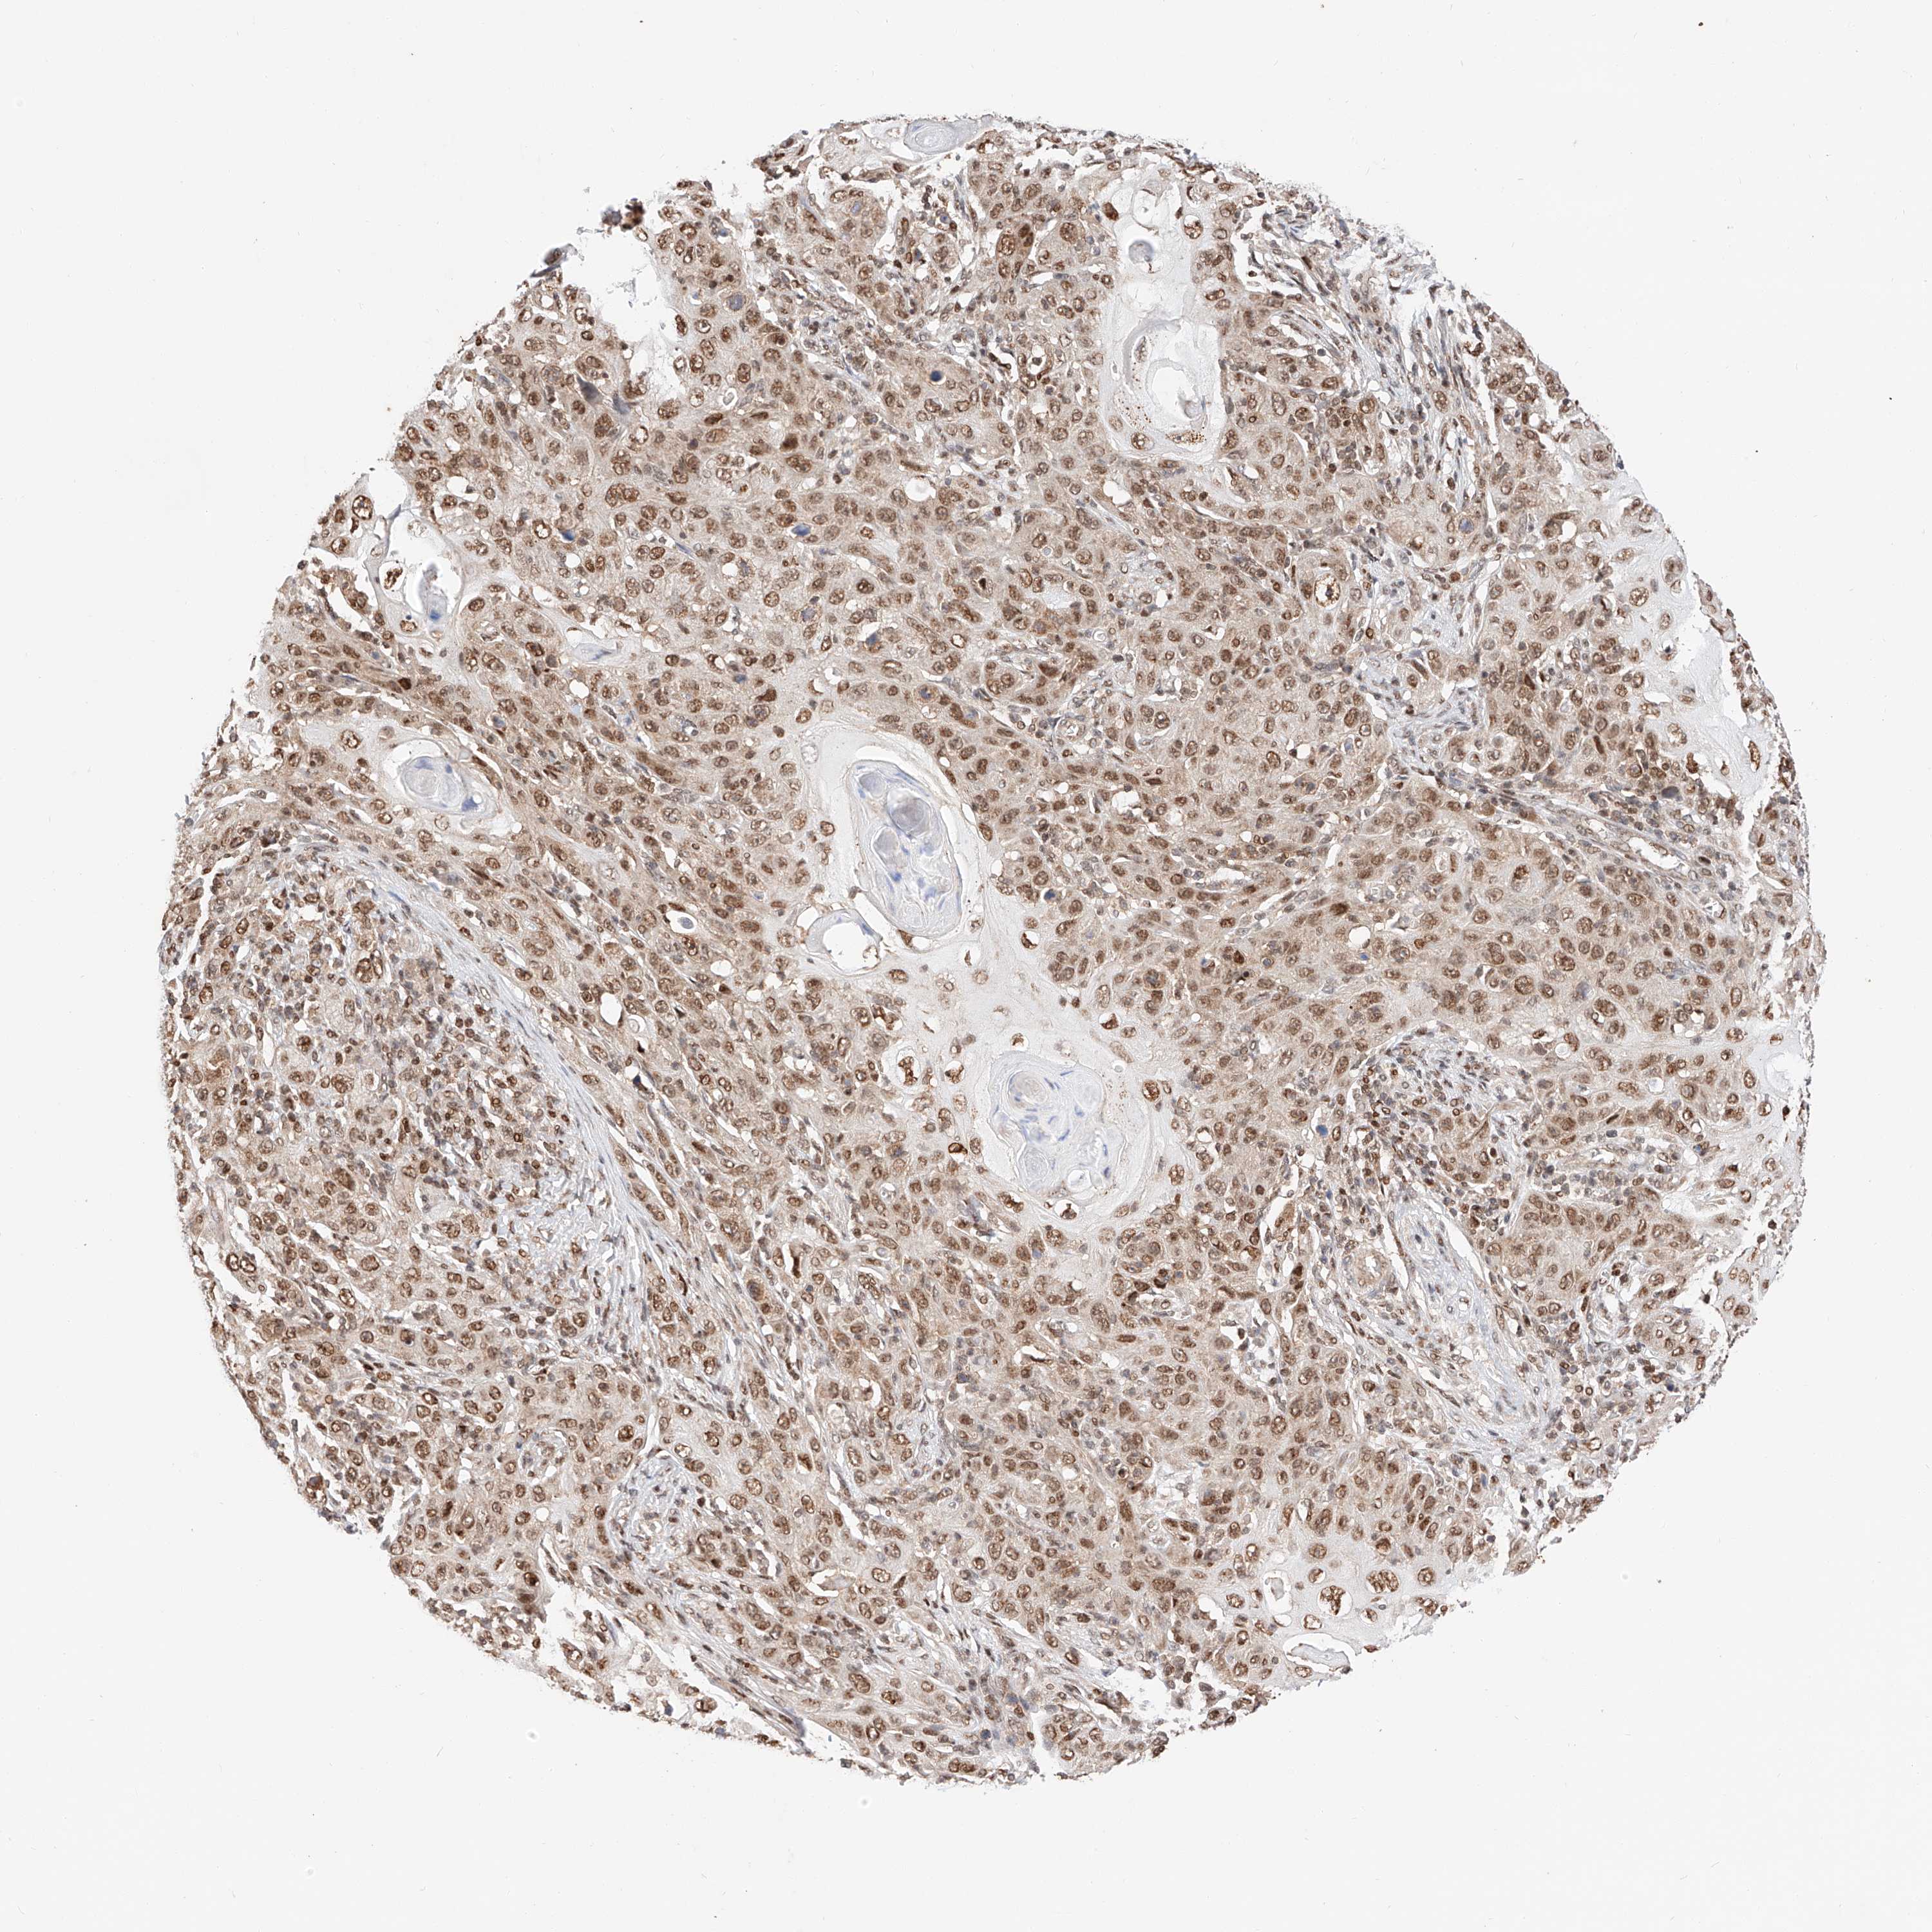

SKIN CANCER - Protein expressioni

A mouse-over function shows sample information and annotation data. Click on an image to view it in a full screen mode. Samples can be filtered based on level of antibody staining by selecting one or several of the following categories: high, medium, low and not detected. The assay and annotation is described here.

Antibody stainingi

Antibody staining in the annotated cell types in the current human tissue is reported as not detected, low, medium, or high, based on conventional immunohistochemistry profiling in selected tissues. This score is based on the combination of the staining intensity and fraction of stained cells.

Each image is clickable and will lead to virtual microscopy that enables deeper exploration of all samples and also displays staining intensity scores, fraction scores and subcellular localization as well as patient and tissue information for each sample.

Antibody HPA028926

Staining

High

Intensity

Strong

Quantity

>75%

Location

Nuclear

Basal cell carcinoma